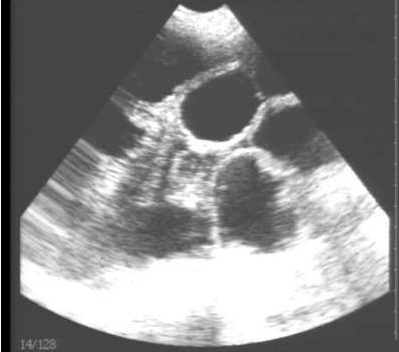

獸用B超機(jī)檢測(cè)母豬空懷圖像

需要注意的是,出現(xiàn)云團(tuán)狀必須雙側(cè)檢查加以確認(rèn).根據(jù)B超機(jī)顯示圖我們大致可以判斷孕齡.圖像呈橢圓或者卵圓形大致為30天左右孕齡;圖像呈橢圓形或者卵圓形外,有明顯發(fā)亮骨骼圖像大致為50孕齡左右;圖像囊胚消失,發(fā)亮處隱約可見(jiàn)竹節(jié)狀東西為成型胎兒骨骼,一般為后期80孕齡以后。一般B超機(jī)成像會(huì)出現(xiàn)三種顏色,白色、黑色、灰色。白色為密度較高的物體,如骨骼或者結(jié)實(shí).黑色一般為液體,包括血液、羊水、組織間隙液體、炎癥病灶等?;疑话銥閷?shí)質(zhì)性物質(zhì),如肌肉。